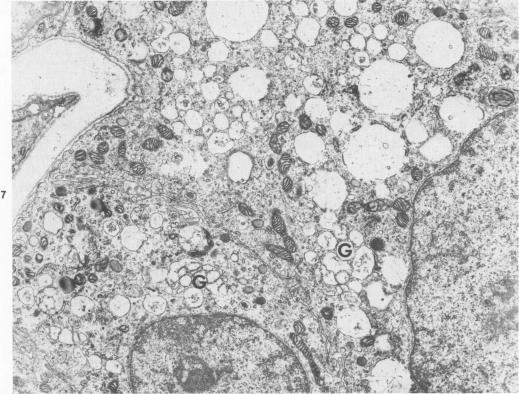

A comparative study of ultrastructural and biochemical effects of Tris and ionophores X537A and A23187 on bovine parathyroid tissue is presented. When parathyroid slices were incubated with 3H-leucine and 3H-lysine for 10 minutes alone or with Tris (50 mM), A23187 (9.5-19 microM) or X537A (8.5-17 microM), the incorporation of the amino acids into radioactive proparathormone (proPTH) was similar, indicating that biosynthesis of the hormone was not affected. After 120 minutes of incubation, however, Tris inhibited the conversion of proPTH to parathormone (PTH), judged by a decrease in cellular and secreted radioactive PTH and a corresponding increase in radioactive cellular proPTH. These changes were accompanied by marked dilatation of Golgi membranes. With both concentrations of A23187 and the low concentration of X537A there were no changes in amounts of radioactive proPTH, moderate decreases in cellular and secreted radioactive PTH, and little discernible distension of the Golgi membranes. At 17 microM X537A there was moderate increase in amount of radioactive proPTH, a marked decrease in amount of radioactive PTH and swelling of the Golgi membranes. Taken together, these findings suggest that Tris inhibited conversion of proPTH to PTH by disrupting the Golgi zone-the site of conversion of proPTH to PTH; that A23187 and the low concentration of X537A decreased production of PTH by enhancing its degradation; and that X537A at the higher concentration acted both by inhibiting conversion of proPTH to PTH and by enhancing the degradation of PTH.

本文介绍了Tris以及离子载体X537A和A23187对牛甲状旁腺组织超微结构和生化作用的比较研究。当甲状旁腺切片单独与3H-亮氨酸和3H-赖氨酸孵育10分钟,或与Tris(50 mM)、A23187(9.5 - 19 microM)或X537A(8.5 - 17 microM)一起孵育时,氨基酸掺入放射性前甲状旁腺激素(proPTH)的情况相似,这表明激素的生物合成未受影响。然而,孵育120分钟后,通过细胞内和分泌的放射性甲状旁腺激素(PTH)减少以及放射性细胞内proPTH相应增加来判断,Tris抑制了proPTH向甲状旁腺激素(PTH)的转化。这些变化伴随着高尔基体膜的明显扩张。使用两种浓度的A23187以及低浓度的X537A时,放射性proPTH的量没有变化,细胞内和分泌的放射性PTH适度减少,高尔基体膜几乎没有明显扩张。在17 microM X537A时,放射性proPTH的量适度增加,放射性PTH的量显著减少,高尔基体膜肿胀。综上所述,这些发现表明,Tris通过破坏高尔基体区域(proPTH转化为PTH的部位)来抑制proPTH向PTH的转化;A23187和低浓度的X537A通过增强PTH的降解来减少PTH的产生;而高浓度的X537A则通过抑制proPTH向PTH的转化以及增强PTH的降解来发挥作用。